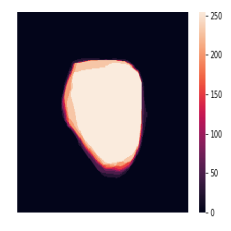

In total, we have generated synthetic polyp images and the corresponding masks. SinGAN-Seg generates random samples with high variations when the input scale is . This variation can be easily recognized using the standard deviation (SD) and the mean mask images presented in Fig 5. The mean and SD images were calculated by stacking the generated mask images corresponding to the synthetic images related to a real image and calculating pixel-wise std and mean. Bright color in std images and dark color in mean images mean low variance of pixels. In contrast, dark color in std and bright color in mean images reflect high variance in pixel values. By investigating Fig 5, we see that small polyp masks have high variance compared to the large polyp mask as presented in the figure.

To understand the difference between the mask distribution of real images and synthetic images, we plotted pixel distribution of masks of synthetic images in Fig 6. This plot is comparable to the pixel distribution presented in Fig 3. The randomness of the generations made differences in the distribution of true pixel percentages compared to the true pixel distribution of real masks of real images. However, the overall shape of synthetic data mask distribution shows a more or less similar distribution pattern to the real true pixel percentage distribution.